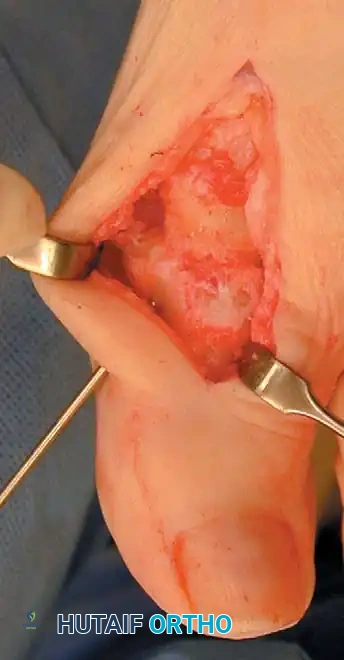

Keller Resection Arthroplasty The Keller procedure combines resection hemiarthroplasty of the fi rst metatarsophalangeal joint with removal of the medial eminence of the fi rst metatarsal (Fig. 78-28). Although removing the base of the proximal phalanx decompresses the joint and mobilizes the hallux, allowing marked correction of valgus, the varus of the fi rst metatarsal is not corrected, and maintaining correction of the valgus of the hallux is diffi cult. Other complications of the Keller procedure have been emphasized in the literature to such an extent (with neither the incidence nor the severity of such complications clearly documented) that the indications for this procedure have been limited severely. In our experience, however, complications are uncommon if patients are selected carefully. Modifi cations in the original technique also have allowed expansion of the indications for the Keller bunionectomy. Candidates for the Keller procedure are patients older than 50 years with moderate-to-severe hallux valgus (30 to 45 degrees); intermetatarsal angles of 13 degrees or less, indicating mild-to-moderate metatarsus primus varus; and pain over the medial eminence with any shoe worn, so the variety of shoes the patient can wear is severely limited. An incongruous fi rst metatarsophalangeal joint caused by

Fig. 78-26 Modifi ed McBride bunionectomy (DuVries; Mann). A, Medial capsule of second metatarsophalangeal joint is sutured to lateral capsule of fi rst metatarsophalangeal joint with interposition of released adductor hallucis. B, Medial capsular resection. C, Confi guration after capsular resection. D, After capsular imbrication, hallux should rest in neutral position or not exceed 5 degrees of varus. E, Postoperative dressing technique (Mann). ( E after Beverly Kessler; courtesy of LTI Medica and The Upjohn Company.) lateral subluxation of the phalanx on the metatarsal head, severe lateral displacement of the sesamoids, and any evidence of degenerative cartilage changes in the joint all are radiographic indications for the Keller procedure. Two modifi cations in technique can expand these indications, however, to include patients with more severe deformities (Fig. 78-29) (but not to include younger patients): fi bular sesamoidectomy and lateral displacement of the fi rst metatarsal. Using these modifi cations, Donley et al. obtained an average 18-degree correction of the metatarsophalangeal angle and an average 6-degree correction of the intermetatarsal angle in 38 patients (50 feet);

95% of patients were satisfi ed with their results. Patients with 50 degrees or more of valgus of the hallux (18 to 20 degrees of varus of the fi rst metatarsal), complete lateral dislocation of the sesamoids, marked degenerative changes, and severe pronation of the hallux may benefi t functionally and cosmetically from alterations of the standard technique.

The following modifi cations of the Keller technique can expand the indications for use with more severe deformities.

REMOVAL OF THE FIBULAR SESAMOID

• When the medial eminence and phalangeal base have been excised, remove the fi bular sesamoid.

• Place a sturdy two-toothed retractor beneath the metatarsal head, and have an assistant lift it dorsally.

• Using a Freer elevator or a small osteotome for its strength, mobilize the fi bular sesamoid (Fig. 78-31A to C). This may be diffi cult in elderly patients with signifi cant deformity and adherence of the sesamoid to the metatarsal head. Lift the metatarsal dorsally for exposure (Fig. 78-31D and E).